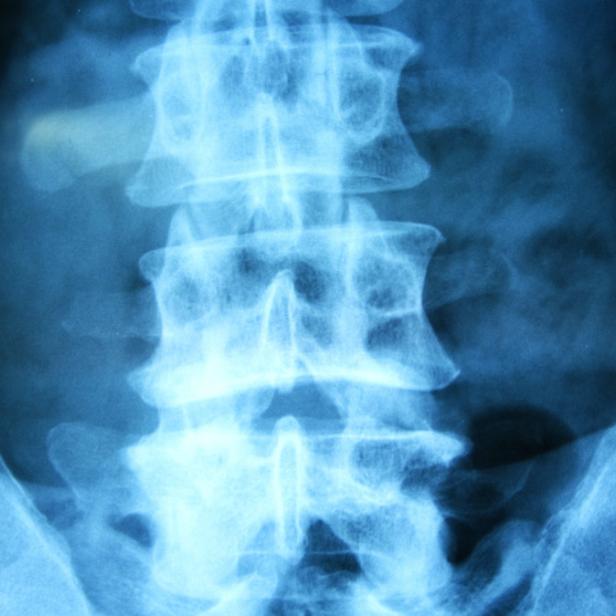

Böser Computer könnte Röntgenbilder verfälschen

Schweizer Wissenschafter zeigen die Möglichkeit auf, der Angriff sei aber noch nicht durchführbar.